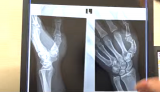

- 加藤の左手親指の骨折レントゲン写真(『エンセン井上Channel』)

- 加藤の膨れ上がった左手親指の付け根(『エンセン井上Channel』)

- 病院では折れて曲がった骨を真っ直ぐにする治療が行われた(『エンセン井上Channel』)

- 左は加藤の幹部。右はエンセンの手。大きさや形がソックリだった(『エンセン井上Channel』)